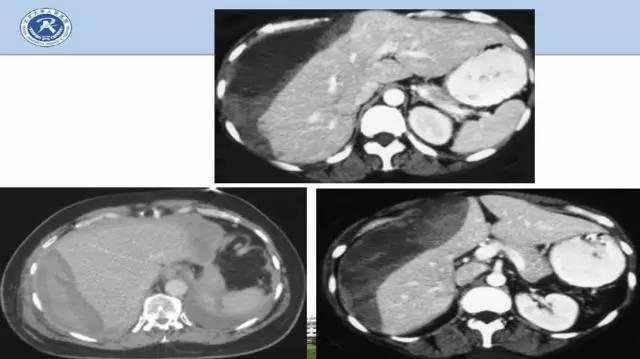

可以通过超声、CT检查来判断肝脏是否完好,一旦有受损,就要尽快接受包括手术在内的各种治疗。下图可以看出,正常肝脏是灰灰的,白色是血管,但如果看到肝脏边缘发黑了,就说明肝脏受损。肝脏比较脆,血液非常丰富,出血就变得非常危险。